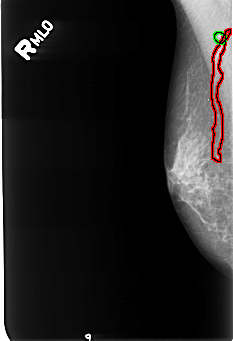

B_3246_1.RIGHT_MLO

FILE: B_3246_1.RIGHT_MLO.OVERLAY

TOTAL_ABNORMALITIES 2

ABNORMALITY 1

LESION_TYPE CALCIFICATION TYPE VASCULAR DISTRIBUTION N/A

ASSESSMENT 2

SUBTLETY 4

PATHOLOGY BENIGN_WITHOUT_CALLBACK

TOTAL_OUTLINES 1

BOUNDARY

ABNORMALITY 2

LESION_TYPE CALCIFICATION TYPE SKIN DISTRIBUTION N/A